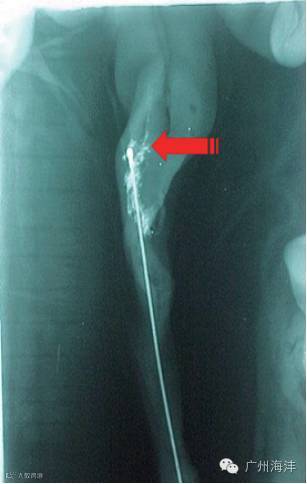

PCAI:子宫颈后人工授精, 与常规子宫颈内授精相比, 在将常规输精管插入子宫颈皱褶后, 再插入一个细的、半软的输精内管, 它比常规输精管长16cm, 可以通过子宫颈皱褶进入子宫体。

子宫颈输精精液的分布情况